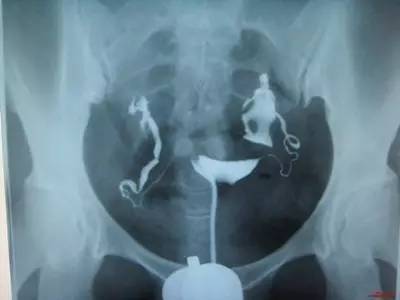

美国试管专家介绍说,输卵管造影术是通过导管像宫腔内及输卵管注入造影剂,利用X线诊断仪行X线透视即摄片,根据造影剂在输卵管及盆腔内的显影情况来了解输卵管是否通畅、阻塞部分及宫腔形态的一种检查方法。